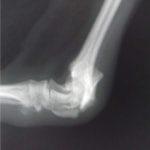

症例3:キルシュナーワイヤーのピンニングによる整復

ペルシャ猫 11ヶ月齢 雄

他院にて左大腿骨遠位の成長板骨折(salter-harrisⅠ型)が認められており、治療相談を目的として来院。当院にて、キルシュナーワイヤーを用いたピンニングにより骨折部位の整復を行いました。術後の経過は良好で、現在も経過観察中です。

術前レントゲン

術後レントゲン